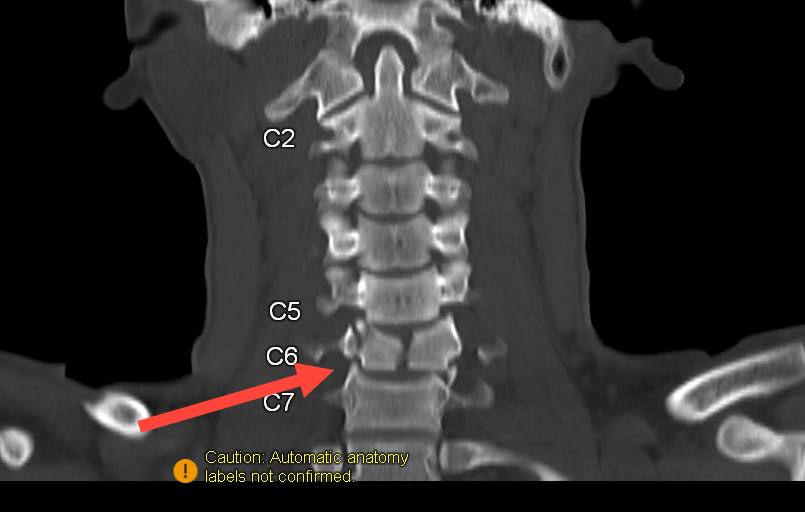

Как рассказали в ДРКБ, произошло это в одном из районов республики. Врачи диагностировали серьезную травму шейного отдела позвоночника. К сожалению, последствия оказались необратимыми: юноша остался глубоким инвалидом.

Фото: 3D-реконструкция травмы шейного отдела пострадавшего ребенка